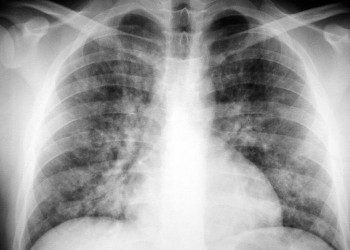

Copiii o aduc la camera de gardă, unde i se efectuează o radiografie care arată infiltrate interstițiale difuze. Testele de laborator evidențiază prezența de aglutinine la rece. Se inițiază tratament cu eritromicină, iar simptomatologia se ameliorează rapid. Care este cel mai probabil agent etiologic al afecțiunii respiratorii acute?